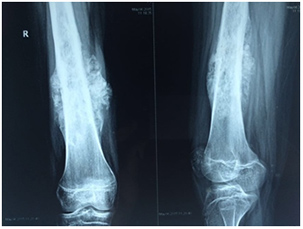

Osteosarcoma or osteogenic sarcoma is the main type of bone cancer. Osteosarcoma is a type of cancer in which tumour cells produce immature bone known as osteoid. Although osteosarcoma is rare, it is the most common childhood bone cancer. Osteosarcoma usually affects the body's long bones near the growth plates, areas where new tissue forms as a young person grow. Most tumours occur around the knee in either the femur or shin bone. Osteosarcoma can also arise from other parts of the body even outside of the bones in the soft tissues, especially in older patients. More males than females get this cancer.

• X-ray is often the first investigations. Sometimes special views are ordered to enable better visualization of bone tumours.